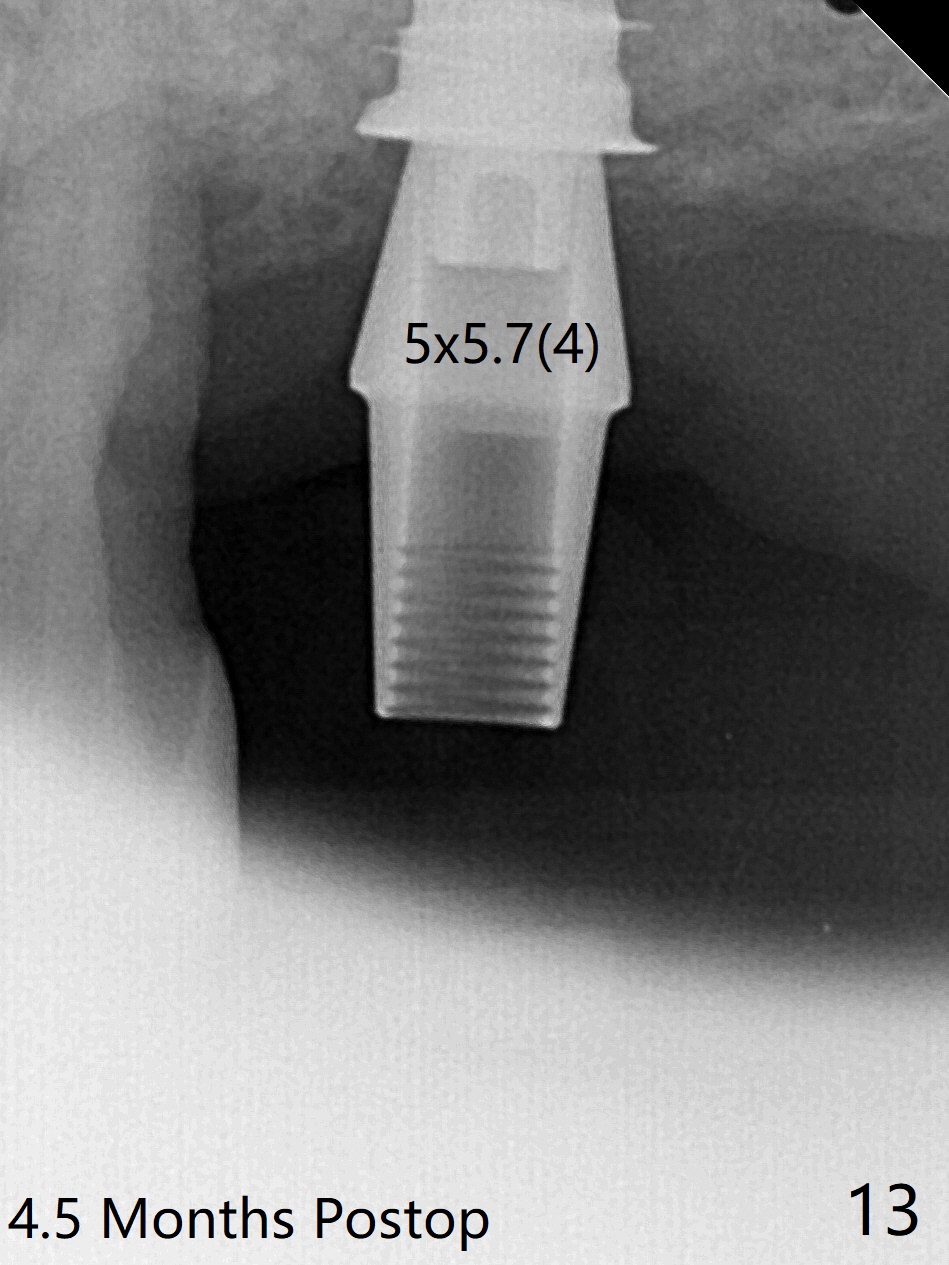

左上7完成初步钻洞,园钻头无法插入导板金属圈,用2.2毫米钻头钻深2毫米,窦膜似乎完整,在没有骨粉情况下,使用4x10毫米报废植体做上颌窦提升(图一),可能一下提升太多,窦膜破了,塞入两小块胶原膜,注入NovaBone

Putty (in

cartridge),植入短小植体(4.5x7毫米,原定(5x8.5毫米)图二),由于稳定性好,使用5.5毫米profile钻头后,放置5.5x4毫米愈合基台(图三)。术后病人没有什么上颌窦不适和分泌物。估计Novo

Bone在上颌窦里凝固了。其实左侧上颌窦粘膜术前增厚(图四,五:L),人工骨仿佛弥撒在上颌窦膜中(图六)。术后一周病人没有任何鼻窦症状。术后4.5月旋转愈合基台时,病人感到疼痛,终止取模(图七),两个月后复诊,做progressive loading。术后5.5月旋转愈合基台时,植体一起出来,但是上颌窦膜没有破,放置大一号植体(报废)扭力不够(图八),再大一号扭力可以(图九),放置愈合帽。由于邻牙长(图九:双箭头),牙周敷料逗留三周不掉(图十:P)。撤除后,伤口愈合正常。The